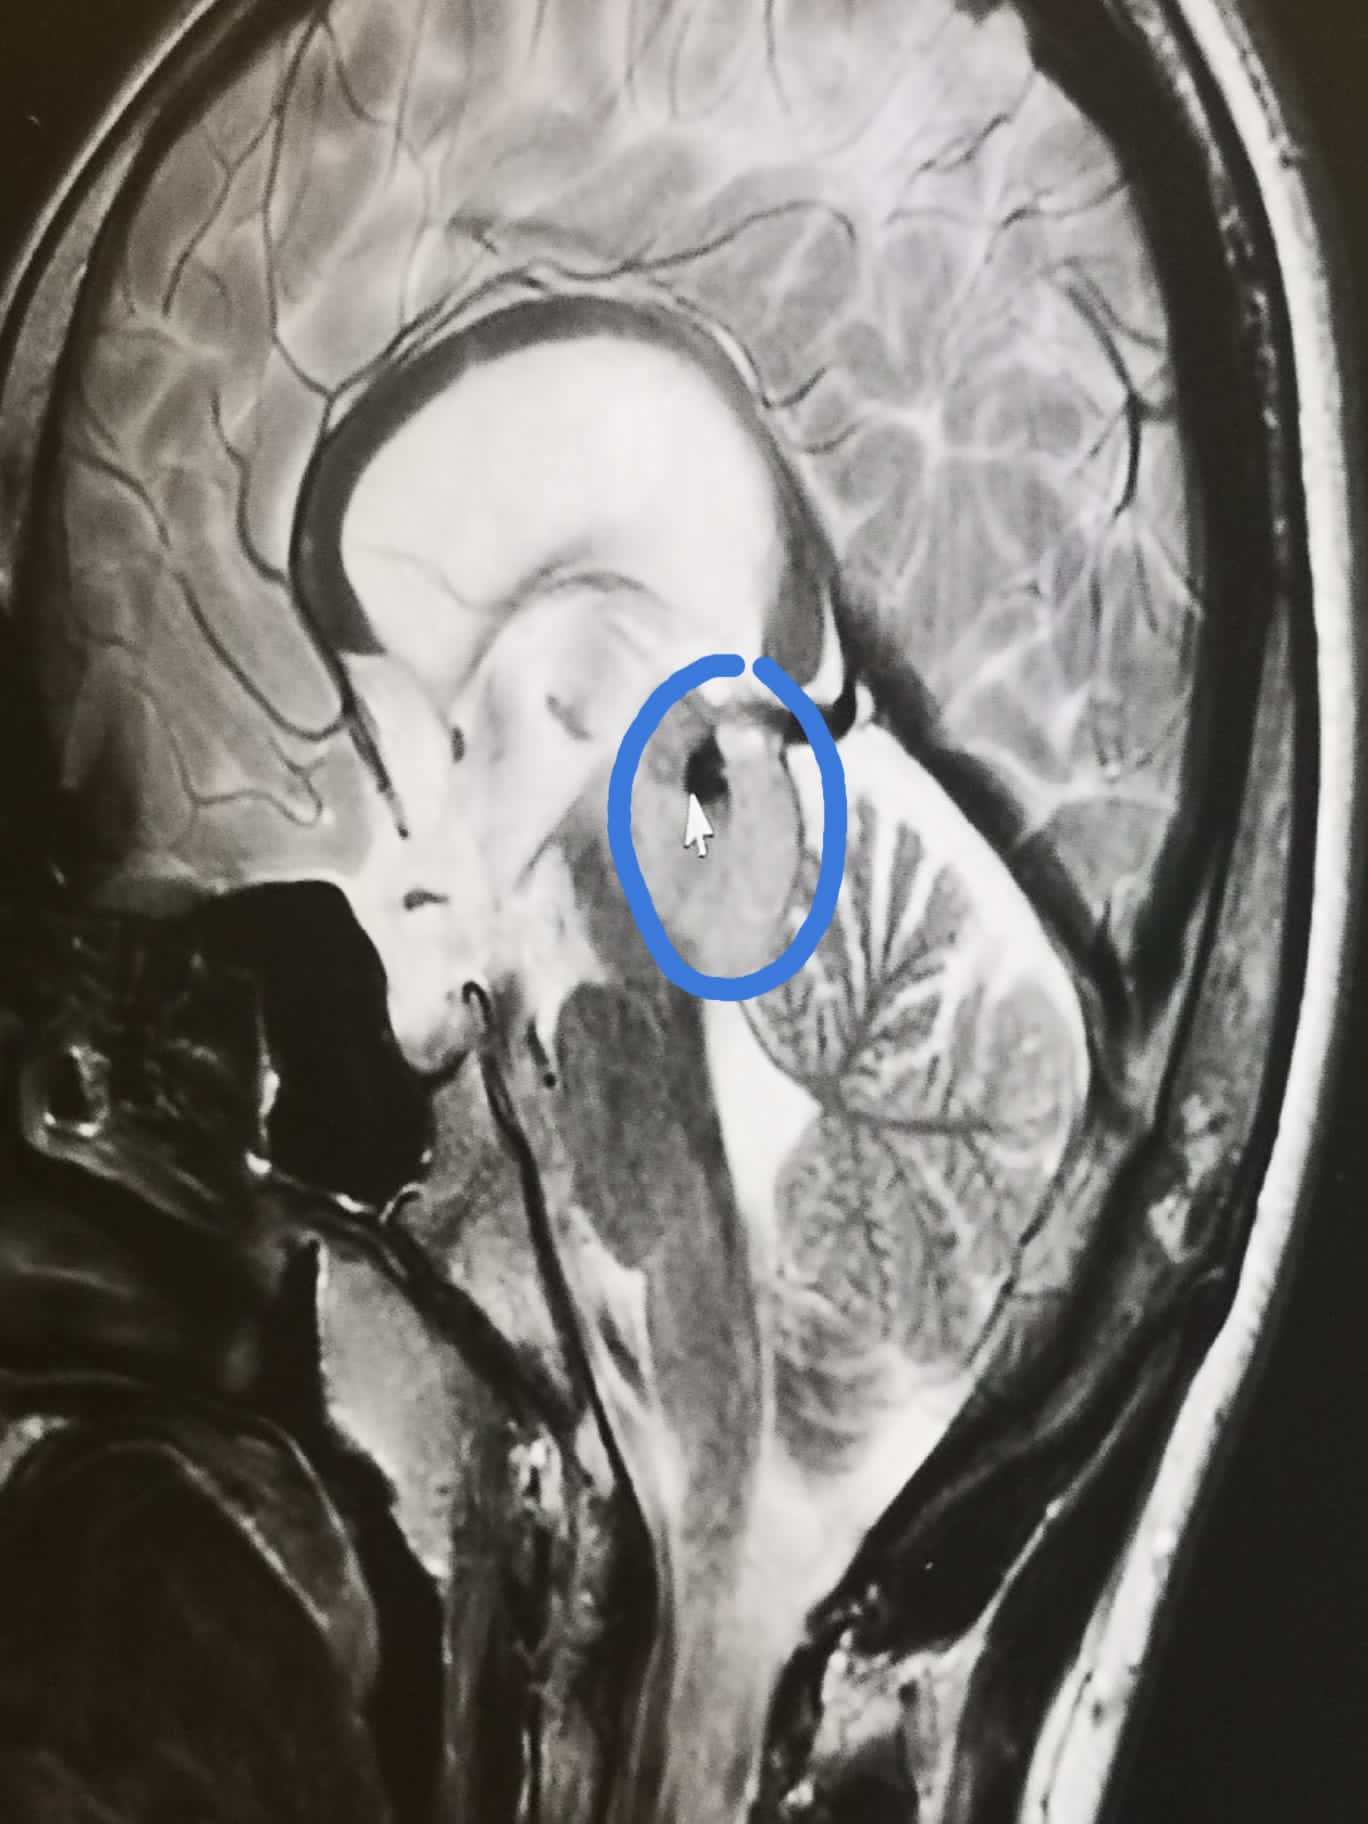

Jake (now 14) was diagnosed with a tectal glioma in August 2015. He was being sick lots so we took him to hospital as the amount of sickness wasn't normal. They said he had food poisoning. 5 days stay in hospital Jake wasn't getting no better and his eyes stopped reacting to light.

Jake was under the local children's hospital already for his eyes because he is fully

blind in his left eye. They told the hospital we were in to do an MRI scan on him and that's when we found out he had

hydrocephalus

and a brain tumour. Jake was then rushed to the local children's hospital for brain surgery which was a success.